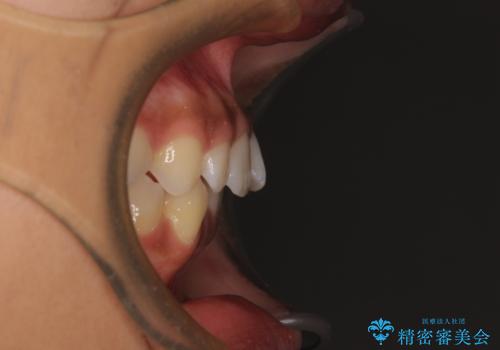

- 上下前歯の叢生を気にして来院された患者様です。

インビザラインでの治療を希望されていて、デコボコの程度が中等度であり、安価なパッケージにて対応可能と判断されたため、インビザライン・モデレートを用いて矯正治療を行うこととしました。